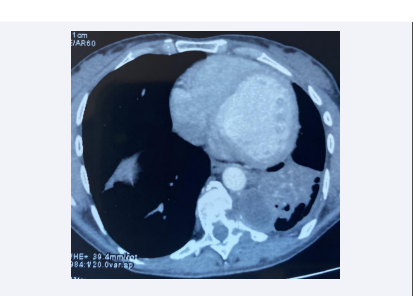

Thoracic CT revealed three left lung cysts associated with cystic formation in the left paravertebral gutters at the level of vertebrae D10-D12, eroding the cortex of the vertebral bodies, the corresponding transverse apophyses and ribs, extended intra-canal with lysis of the posterior arch of D10 and a calcified cyst of the hepatic dome. Flexible bronchoscopy showed complete obstruction of the left lower lobar by whitish membranes that were difficult to remove, with no other visible abnormalities. The bronchial aspiration fluid was tested positive for scolex, as was hydatid serology. Cerebral CT, abdominal ultrasound and cardiac ultrasound revealed no cystic images. The diagnosis was multiple pulmonary hydatidosis, including one paravertebral and one calcified hepatic hydatid cyst. Treatment consisted of concomitant resection of the pulmonary hydatid cysts and the paravertebral hydatid cyst [Figure 4],

In our patient, the paravertebral hydatid cyst was asymptomatic, discovered on thoracic CT [Figure 1 and Figure 2].

Frontal section of thoracic tdm showing left pulmonary  hydatid cysts with a homolateral paravertebral hydatid cyst.

Figure 1: Frontal section of thoracic tdm showing left pulmonary hydatid cysts with a homolateral paravertebral hydatid cyst